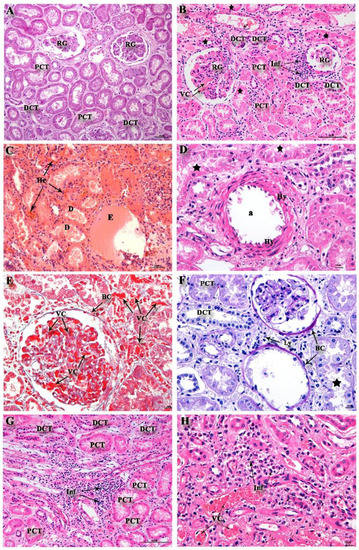

| Region | Injury | Control | Cases | p-Value |

|---|---|---|---|---|

| Cortical | Vascular congestion | 0(0–0) | 1(0–1) | 0.0040 |

| Degeneration | 1(0–2) | 4(4–4) | <0.0001 | |

| Infiltrates | 2(0–2) | 3(2.75–4) | <0.0001 | |

| Medullary | Vascular congestion | 1(0–2) | 0(0–1) | 0.1280 |

| Infiltrates | 2(1–2) | 4(3–4) | <0.0001 | |

| Necrosis | 2(0–3) | 4(2–4) | 0.0008 |